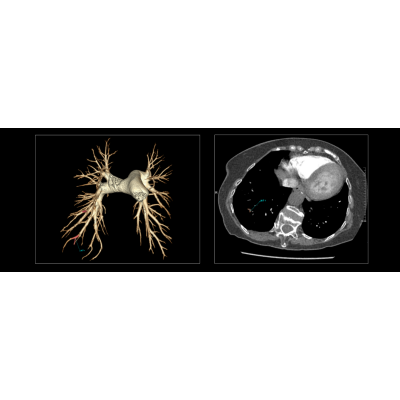

联影智能CT肺栓塞智能分析系统能够提供PE分诊预警、栓子检出和量化、肺血管智能分割和重建等功能,帮助医生及时诊断PE,鉴别诊断急性胸痛患者。同时,肺栓塞智能分析系统能够自动、准确地进行心室测量和肺动脉测量,提示右心室增宽和肺动脉增宽等PE相关风险征象,为早期PE检测和风险分层提供参考,辅助医生制定更优的诊疗方案,改善预后。

联影智能CT肺栓塞人工智能可一键智能分割、重建完整肺血管和栓子,360°展示肺动脉走行和栓子分布位置;高灵敏检出和定位栓子,提供量化分析,并自动计算RV/LV和PA/Ao,全面辅助诊疗,为PE的早期识别和临床风险分层提供强有力的智能工具;而快速分诊预警更是能够助力危急患者尽早进入诊疗环节。此外,AI可智能生成文本报告和归档图像,支持一键胶片打印。通过对救治全流程的加速优化,AI能够辅助医生快速识别隐匿肺栓塞,让胸痛患者跑赢生死竞速。